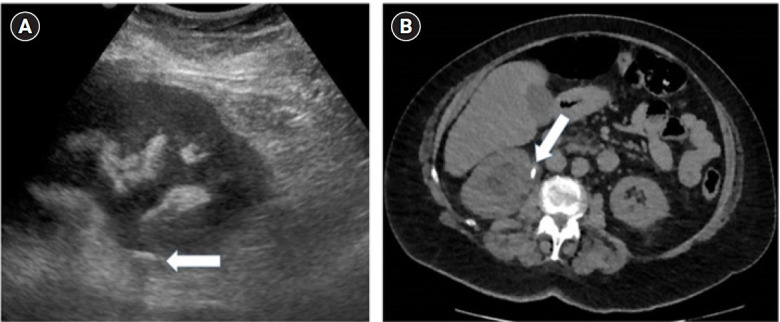

Symptomatic urolithiasis is a common cause of emergency department visits, with noncontrast computed tomography considered the imaging gold standard. According to the current guidelines, point-of-care ultrasound (POCUS) is limited to evaluating hydronephrosis as a secondary sign of acute ureteral stones. However, the use of POCUS to detect ureteral stones may lead to decreased radiation to the patient and a more rapid diagnosis. This case series describes 10 patients with suspected symptomatic urolithiasis who were diagnosed accurately by emergency physicians using POCUS to detect obstructive ureteral stones. In three of the cases, POCUS significantly changed the patient's management. This article also describes the proper techniques for the emergency physician to learn to master POCUS for ureteral stone detection.